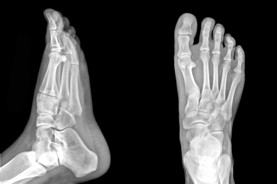

The Foot Institute is an association of Calgary Doctors specializing in the medical treatment of the foot and ankle, and is one of the largest groups of foot specialists in Alberta.

The Calgary Foot Institute is dedicated to the medical and surgical treatment of the foot. Our mandate is to provide the best possible medical, surgical and preventative treatment available for our patients. We do this by providing well-trained Doctors who are committed to treat and prevent all types of foot pain, biomechanical disorders, as well as all other problems relating to the feet.

At the Calgary Foot Institute, our Doctors are trained to specifically treat problems associated with your feet or ankles. Below are several of the most common problems that we see on a day to day basis: